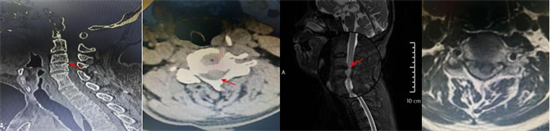

術(shù)前影像資料顯示C3/C4椎間盤突出、極重度頸椎椎管狹窄、C5/6椎體融合

患者李某,70歲,因“四肢乏力、行走不穩(wěn)1年,加重1個月”入住衡南縣人民醫(yī)院骨科二區(qū),入院檢查診斷為:脊髓型頸椎病、頸椎椎管狹窄癥(C3/C4極重度)、慢性不完全性四肢癱。其中C3/4節(jié)段椎管占位率超過50%以上,脊髓受壓極其嚴重,若病情繼續(xù)進展,可能導(dǎo)致高位截癱甚至呼吸衰竭,危及生命。且李某還存在C5、6節(jié)段先天性融合,短頸畸形,進一步增加了術(shù)中暴露和置釘?shù)碾y度,對主刀醫(yī)生的經(jīng)驗、技術(shù)及團隊配合要求極高。